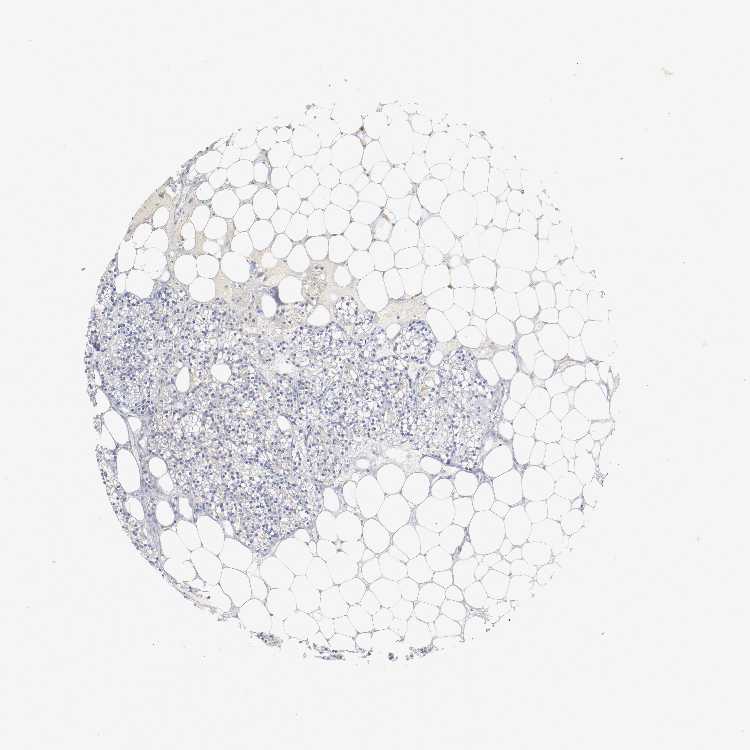

TISSUE PRIMARY DATA PARATHYROID GLAND Show tissue menu

PARATHYROID GLAND - Antibody stainingi

Antibody staining in the annotated cell types in the current human tissue is reported as not detected, low, medium, or high, based on conventional immunohistochemistry profiling in selected tissues. This score is based on the combination of the staining intensity and fraction of stained cells.

Each image is clickable and will lead to virtual microscopy that enables deeper exploration of all samples and also displays staining intensity scores, fraction scores and subcellular localization as well as patient and tissue information for each sample.

Antibody HPA004332

Glandular cells Not detected